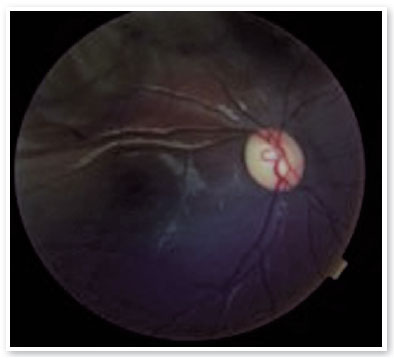

On ophthalmologic examination, static refraction of +1.50D spherical in both eyes (AO), with visual acuity of 20/20 in the right eye (RE), partial 20/100 in the left eye (LE) and changes in the Ishihara color test. There were no changes in the extrinsic ocular motility. On biomicroscopy, isochoric and photoreactive pupils were observed, with hamartomatous irian nodulations in AO, which were more concentrated inferiorly and suggestive of Lisch nodules (Figure 1). Gonioscopy demonstrated an open angle to the ciliary body in AO, and fundoscopy demonstrated a more pronounced bilateral optic papilla pallor in LE, with an excavation/disc ratio of 0.4 RE and 0.8 LE (Figures 2 and 3). The intraocular pressure was 12 mmHg in AO. On general inspection, the presence of numerous hyperchromic café au lait spots distributed on the trunk (Figure 4) and back (Figure 5) was noted.

Figure 2. Color retinography of the right eye.

Figure 3. Color retinography of the left eye.